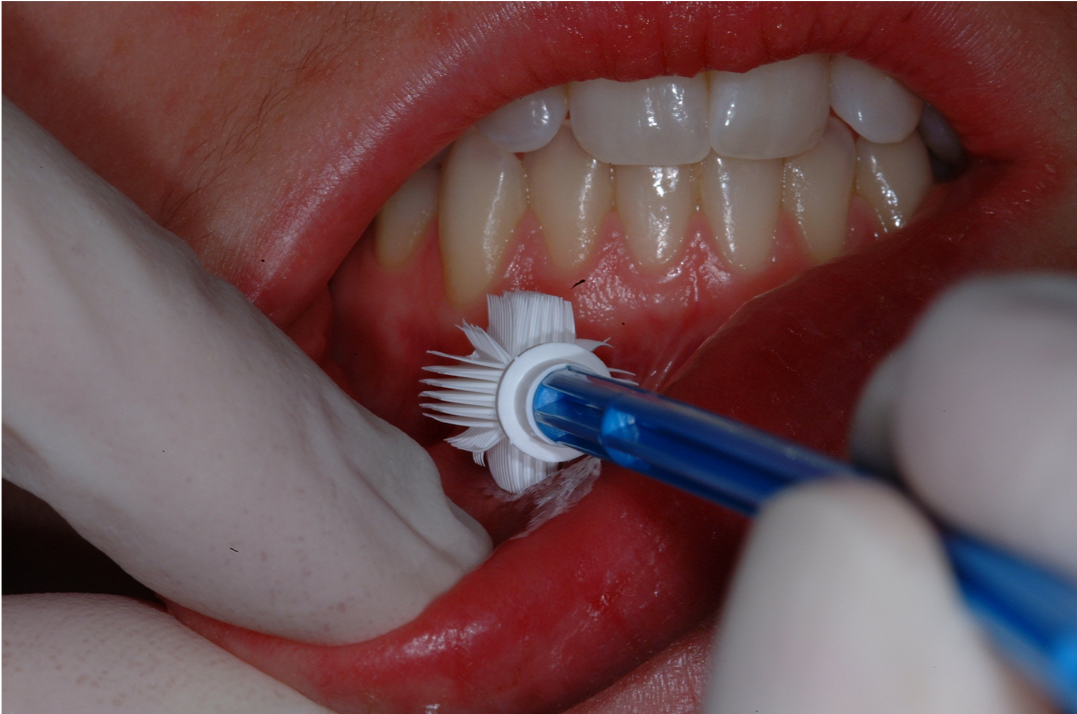

An excisional biopsy removes the entire lesion and a border around the lesion. An incisional biopsy removes part of the lesion for diagnostic purposes. In a brush biopsy (Figure 3), a small brush is used on the lesion to collect material for the biopsy that may provide helpful information on infectious and noninfectious oral diseases. Fine-needle aspiration biopsy technique (Figure 4) is used on salivary gland masses and enlarged lymph nodes. Fine-needle aspiration involves a thin hollow needle being inserted into a mass to extract cells or fluids. The patient rinses the mouth with chlorhexidine for about 60 seconds, and the area is then numbed with local anesthetic. A 22-gauge needle is normally used to collect a sample, which is then fixated to a slide for examination by an oral pathologist.

Fig 3. Brush biopsy.

Figure 3